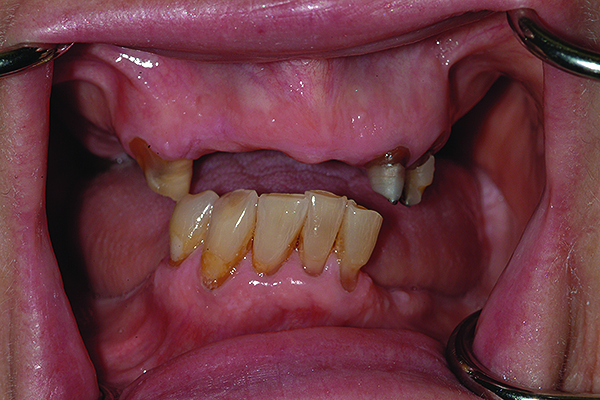

The patient’s intraoral condition.

Figure 18